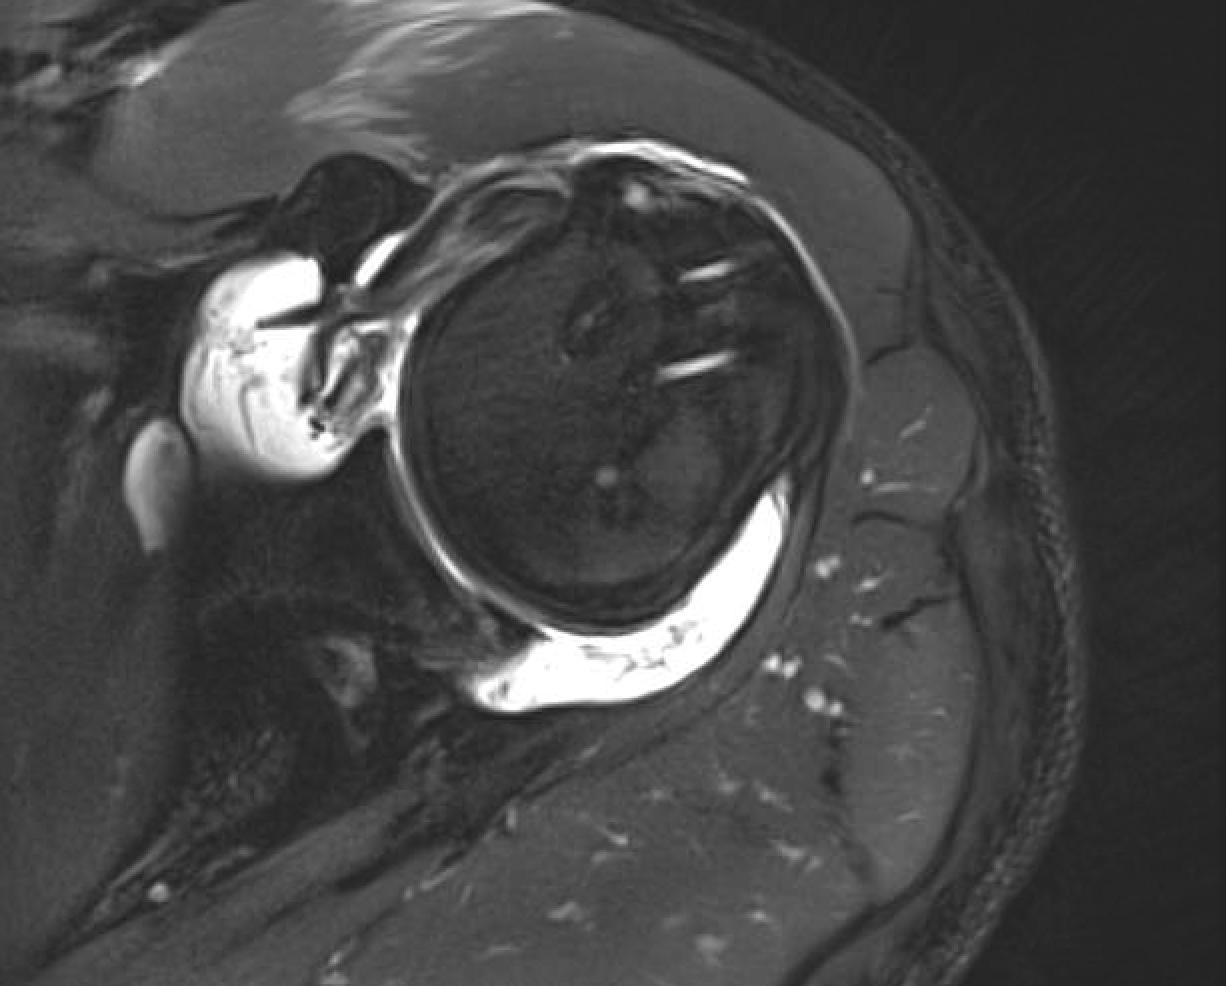

From myloview.com

Rotator cuff slap tear torn pain injury tendon muscle joint xray Range Of Motion Rotator Cuff Tear R o tat o r c u f f h o m e e x e r c i s e p r o g r a m. Arthroscopic rotator cuff (arc) clinical trial. Before doing the following exercises, warm up. R o tat o r c u f f h o m e e x e r c i. Range Of Motion Rotator Cuff Tear.